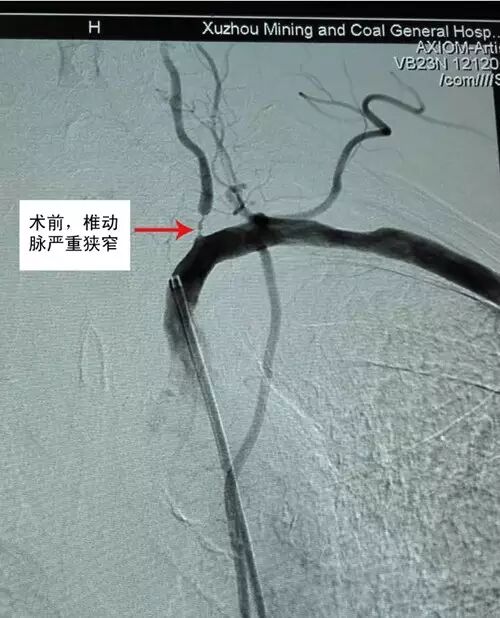

66岁的李大爷患者,一直有高血压,平时经常出现发作性黑矇,前两天因为头晕、呕吐被送到徐矿总医院神经内科治疗,经仔细检查病人后,考虑其患有短暂性脑缺血发作(TIA)疾病,进一步进行血管造影检查提示患者脑部供血情况很差,四条脑部大血管当中左侧椎动脉和左侧颈动脉有重度狭窄,单纯用药物治疗的情况下患者的病情仍有反复发作,如不进行进一步治疗,患者甚则会出现中风偏瘫或昏迷不醒。

神经内科陶中海主任与家属反复沟通后,制定了详尽周密的治疗方案,为李大爷进行颈部动脉内支架植入术,术后患者恢复良好,头晕逐渐缓解,更重要的是,支架置入后通过物理压迫作用,稳定斑块,扩张狭窄的动脉,预防了严重中风的发生,患者很快好转出院。